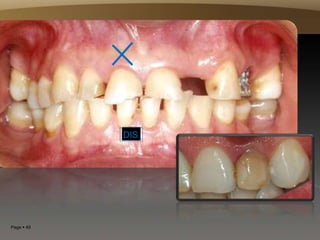

DES

Page  49

DIS